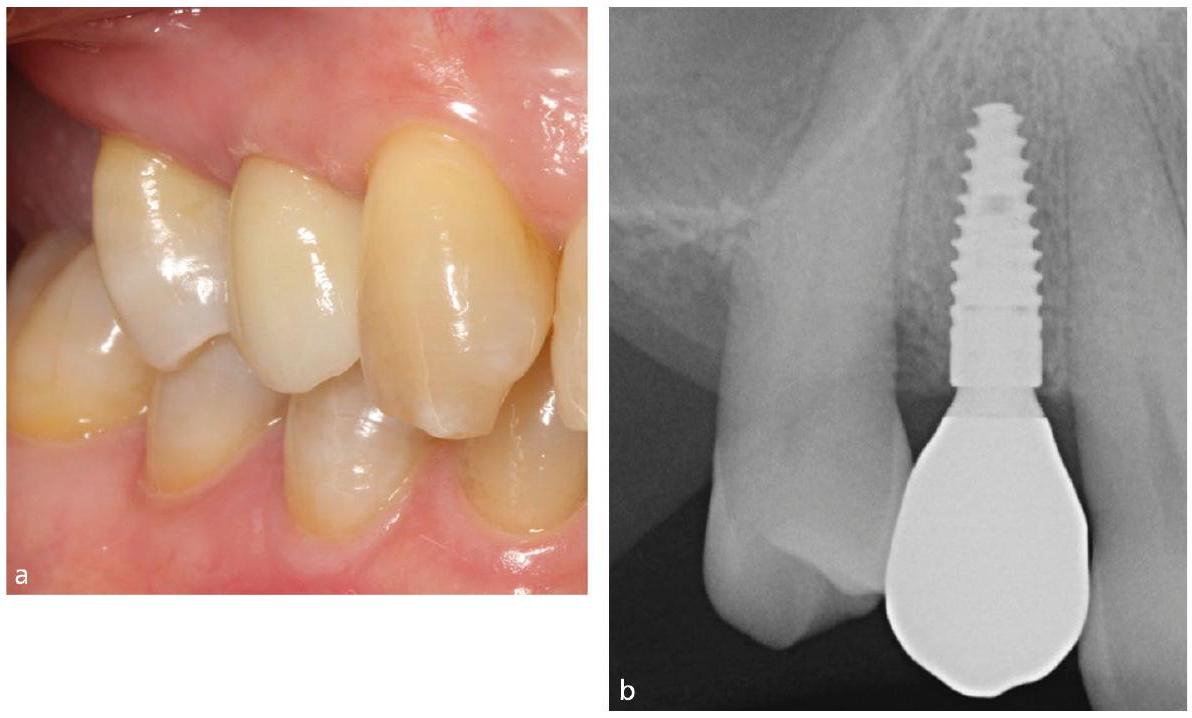

التهاب اللثة، وهو مرض التهابي مزمن تسببه البكتيريا، يتميز بتراكم أنواع الأكسجين التفاعلية (ROS) في مناطق محددة، مما يؤدي إلى استجابة التهابية، والتي بدورها تؤدي إلى تدمير الأنسجة الداعمة للثة. لذلك، فإن استخدام مضادات البكتيريا، والتخلص من ROS، وتقليل الاستجابة الالتهابية، وتنظيم البيئة الدقيقة للثة، وتخفيف امتصاص العظم السنخي هي طرق فعالة لعلاج التهاب اللثة.…